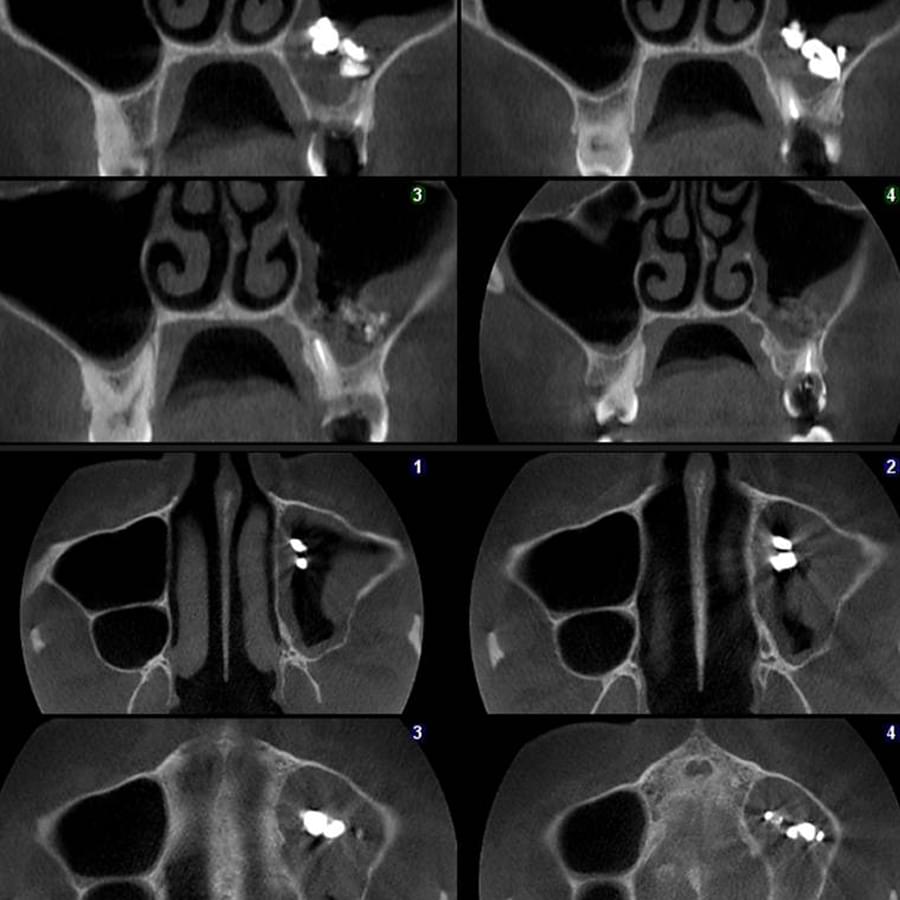

Ми розуміємо, наскільки важлива деталізація в ендодонтії та терапевтичному лікуванні.

Завдяки флагманському обладнанню PLANMECA, ми отримуємо знімки з мінімальним рівнем шумів та

високою роздільною здатністю, що дозволяє чітко візуалізувати морфологію кореневих каналів,

приховані каріозні порожнини та стан періапікальних тканин.

Крім того, ми маємо власний сервер, на

якому створюємо окрему скриньку для кожного лікаря, що забезпечує максимальну зручність та

ефективність роботи.